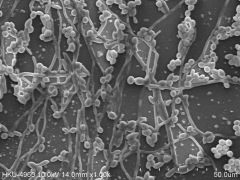

Magnification of the plastic surfaces (by scanning electron microscopy) confirmed that exposure to 3 µg/mL purpurin prevented the formation of biofilms and disrupted pre-formed biofilms. Furthermore, tentacle-like filaments (hyphae) that normally project out from C. albicans cells in biofilms were no longer present.

Filaments were also absent when cells were grown on a gel or in a liquid containing purpurin in addition to nutrients that would normally encourage filamentation.

The ability of C. albicans to grow in filament form and develop into biofilms on a plastic surface (left photo) is blocked by the addition of purpurin (right photo).